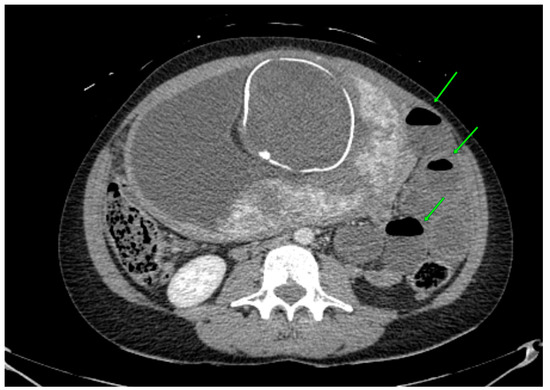

Meckel’s diverticulum (MD) is the most common congenital anomaly of the gastrointestinal tract with a 1–3% prevalence in the general population. The surgical management of symptomatic MD is well described in the literature, but there is still no consensus on the indication for prophylactic resection of incidental asymptomatic MD. To address this issue, we extensively reviewed the current literature and report our experience with laparoscopic management of an unusual case of MD causing ileal volvulus and acute peritonitis two weeks after a laparoscopic appendectomy for acute gangrenous appendicitis performed in another hospital. A 50-year-old man presented to the emergency department with acute and severe abdominal pain, vomiting, and constipation. He had undergone a laparoscopic appendectomy for acute appendicitis two weeks before in another hospital. The patient was apyretic, distressed, and seeking an antalgic position. The abdomen was mildly distended and tender, and the Blumberg sign was mildly positive in the central quadrants. The clinical picture deteriorated with fever, peritonismus, and leukocytosis. A CT scan showed an ileo–ileal adhesion near the ileocolic junction and dilatation of the upstream loops with the air–fluid levels. Through an urgent laparoscopy, a necrotic mass, the MD, was wedge-resected, and the surrounding ileal volvulus derotated. The postoperative course was uneventful. There is no definitive consensus on the appropriate management of incidental asymptomatic MD, although several studies have attempted to identify guiding criteria. Features of the MD, the patient’s risk factors, clinical presentation, and surgical approach need to be considered to establish definitive guidelines for the management of incidental asymptomatic MD. In the absence of definitive guidelines, personal expertise and judgement are the main resources for the surgeon approaching an incidental asymptomatic MD. Full article